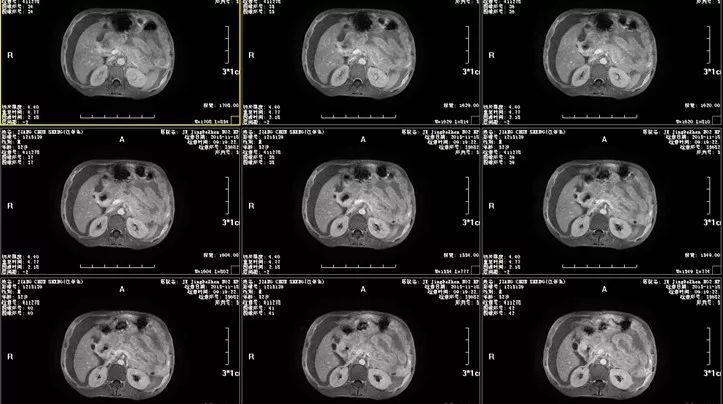

腹部MRI检查已有阳性发现,紧接着行MRI增强扫描以进一步明确诊断,腹部MRI增强示:1.肝门部及十二指肠球部占位,考虑十二指肠来源恶性肿瘤可能,肝尾叶占位,转移瘤可能,建议进一步检查;2.大网膜及腹膜转移,左侧腹壁转移;3.大量腹水。

图三 腹部MRI增强扫描图